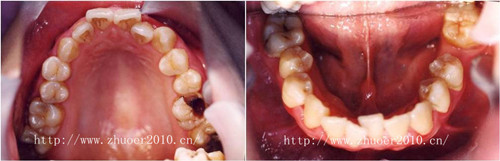

矫治结束

矫治前后口内对比